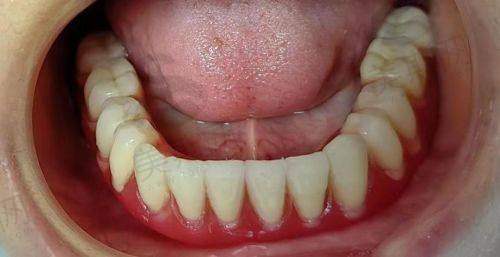

5. 牙周治疗:开展牙周基础治疗、龈下刮治、牙周手术等,采用超声波洁牙结合手工清创,有效去除牙结石和菌斑,治疗牙周炎、牙龈炎等疾病,预防牙齿松动脱落。